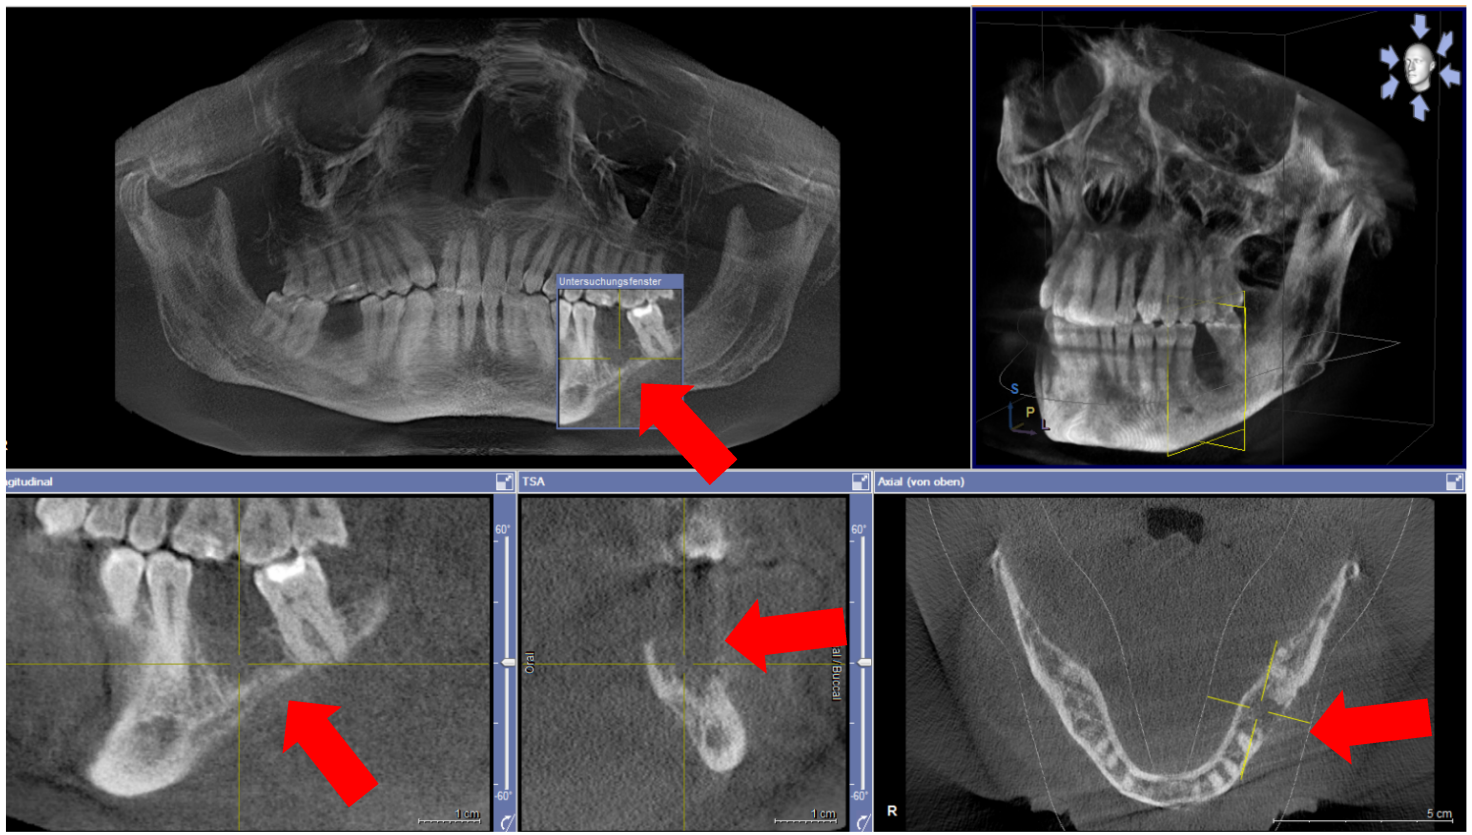

Five months after dismission, the patient was re-admitted to the craniomaxillofacial department with exposed mandibular bone in the area of the extracted first left molar and recurring pain (Figure 2 [Fig. 2]). No signs of mucosal abscess or purulent discharge were detected. The clinical and radiographic examination revealed mandibular osteonecrosis and the patient underwent surgery under general anesthesia after 24 hours of preoperative intravenous antibiotic treatment under hospitalization. This involved partial decortication of the infected mandible region (the residual anterior-posterior alveolar process and the bicortical plate exposed to vital bone) with preservation of the alveolar inferior nerve and the basal cortical margin. After resection, residual infected and necrotic tissues were removed from the remaining avital bone surface by a rotating burr and diamond burr in an attempt to prevent recurrence of osteomyelitis. The wound was closed after periosteal releasing incisions to achieve a tension-free adaption of the soft tissues. As described earlier, an adjuvant cycle of antibiotics was administered and a nasogastric tube was fitted under hospitalization for further 7 days. The local treatment consisted of irrigating the mouth with chlorhexidine and appropriate mouth hygiene. After hospitalization, no more antibiotics were administered. On review, there was a considerable improvement in the patient’s physical condition; the systemic symptoms had objectively subsided and the pain reduced, decreasing the analgesic intake. Two weeks post-operation, we noticed a complete remission of the clinical symptoms, without further dehiscence of the alveolar bone and the soft tissues. A postoperative orthopantomograph was performed 3 months after surgical decortication showed sufficient alveolar bone healing without radiologic signs of osteonecrosis.

Figure 2: Cone Beam Computed Tomography (CBCT) with display of subsequent osteonecrosis of the lower left mandible in region 036 (red arrows)